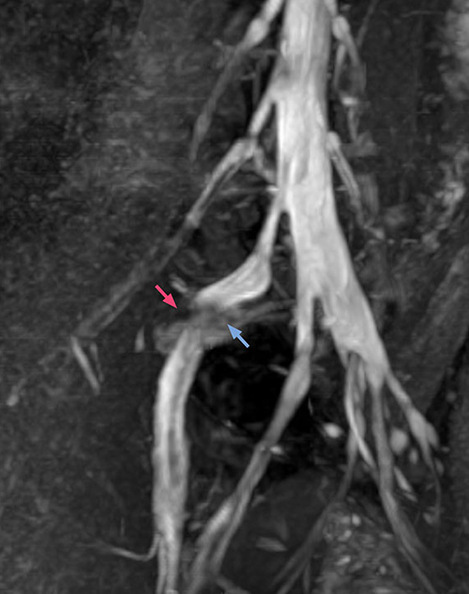

“In patients with lower extremity neurological symptoms, NerveVIEW helps us to determine the disease matching the patient’s symptoms by directly visualizing the nerves. We use the sequence mainly, when there is suspicion of intraforaminal stenosis, extraforaminal stenosis or lateral disc herniation, which is often based on routine T2- and T1-weighted images. Additionally, the excellent depiction of the course of nerves makes NerveVIEW a good navigator when applying treatment such as block therapy or surgery.”

“Before NerveVIEW, diagnosis by MRI alone was sometimes difficult, unless there was a strong suspicion based on clinical symptoms,” says Shoji Yabuki, MD, DMSc, Orthopedic surgeon at Fukushima Medical University School of Medicine. “This is why we routinely perform selective lumbosacral radiculography (nerve root block) and x-ray in such cases. However, radiculography can only depict nerves as far as the contrast agent reaches. When a nerve is distorted by compression, the contrast agent will not pass through this compressed area, preventing us from evaluating the full nerve compression.”

“In such case, we would then browse through axial T2-weighted MR images slice by slice and mentally reconstruct the actual situation based on both radiculography and MRI. Fortunately, NerveVIEW can now very well show nerve courses and presence of nerve compression or edema in one single image series.”

“We have often seen NerveVIEW directly depict details of the nerve compression that were not observed by radiculography. Therefore, we think that with NerveVIEW we can reduce the number of invasive examinations, especially for some patients with lumbar plexus symptoms.”

The key concept in MR neurography, Dr. Yabuki stresses, is the ability to directly visualize spinal nerves, versus inferring the presence of pathology indirectly. “Before NerveVIEW, we estimated compression of the nerve by looking for the presence or absence of fat signal on other MR images,” he says.

“For example, in sagittal images, when the presence of fat is observed in the intervertebral foramen, it suggests that there is a margin around the nerve. Similarly, the absence of fat indicates that the nerve is being compressed. So, we used to deduce nerve compression indirectly. With NerveVIEW, however, we can observe the condition of the nerves directly, regardless of the presence or absence of fat. We always prefer such direct observation of anatomy over having to make an inference about it.”

“NerveVIEW is really useful for those cases where a nerve disorder is strongly suspected based on the clinical examination but our regular MRI images do not show any findings. These atypical herniations and spinal canal stenosis, occurring in 5% to 15% of the total lumbar herniation/stenosis cases are our main target when using NerveVIEW,” says Dr. Yabuki.

“Although symptoms of typical disc herniation and atypical hernia are very similar, the actual site of herniation is different. It is therefore important to characterize the nerve’s condition both inside and outside of the intervertebral foramina.